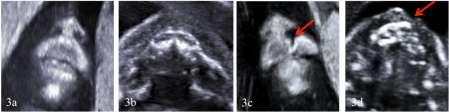

Základem pro vyšetření obličeje plodu je standardní dvojrozměrné (2D) ultrazvukové vyšetření (obrázek č. 3). Obličejové rozštěpy se při něm nejčastěji zjistí v období okolo 20. týdne těhotenství, kdy se u všech těhotných žen v České republice provádí screening vrozených vad plodu. V případě větších obličejových rozštěpů (oboustranný rozštěp rtu a patra) lze vadu často zachytit i dříve, a sice při ultrazvukovém screeningu Downova syndromu (takzvaný prvotrimestrální NT screening, NT plus screening) v jedenáctém až čtrnáctém týdnu těhotenství.

Obrázek č. 3.: Standardní dvojrozměrné (2D) ultrazvukové vyšetření rtu, čelisti a patra plodu ve druhém trimestru těhotenství. Normální nález na rtu v koronálním řezu obličejem plodu (3a) a na rtu, čelisti a patře plodu v transversálním řezu obličejem plodu (3b). Zobrazení malého rozštěpu rtu v koronální (2b) a transversální (2c) rovině vedené obličejem plodu. Šipky na obrázku 3c a 3d směřují k místu rozštěpu rtu.

(Foto: MUDr. Veronika Frisová, Profema)